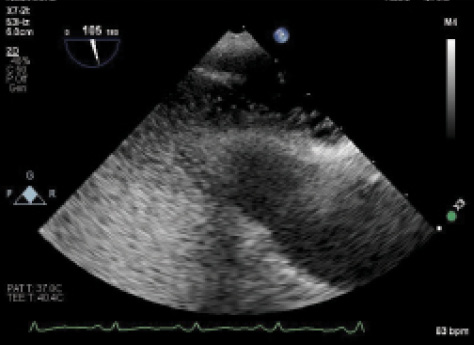

Figure 1. PFO with atrial septal aneurysm. There is wide opening of the septum primum, much larger than is usually seen with most PFOs.

Now, 2 years later, the patient wishes to start a family and is reconsidering her aspirin therapy. No additional events have been reported since the patient has been off contraceptives. TEE was performed again and showed a large PFO with atrial septal aneurysm (Figure 1) and large right-to-left shunt (Figure 2). Treatment proceeded with implantation of a 35-mm Amplatzer PFO occluder (Abbott Vascular) without any complications (Figure 3).